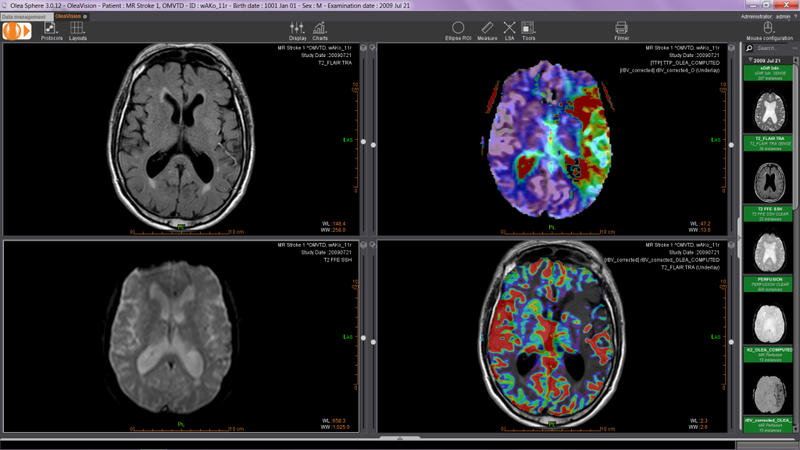

Chụp cộng hưởng từ MRI:

MRI sử dụng sóng vô tuyến và nam châm mạnh để cho ra hình ảnh chất lượng và chi tiết về não bộ. Xét nghiệm này có thể được sử dụng sau khi tình trạng của bệnh nhân đã ổn định hơn hoặc các triệu chứng không được cải thiện sau thời gian nghỉ ngơi và điều trị ban đầu.

cac-hinh-anh-chan-thuong-so-nao-2Phương pháp chụp cộng hưởng từ MRI để xét nghiệm hình ảnh chấn thương sọ não